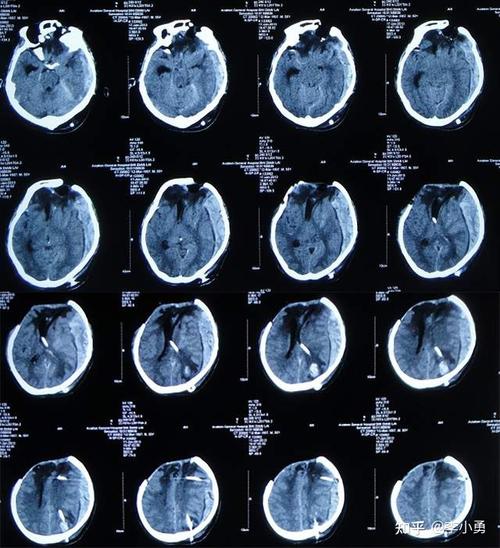

38岁孩子妈妈徐女士,原为一个普通家庭主妇,在医院查出患有肾结石。决定年后做微创手术,家住七台河的她,于2018年3月26日来到哈尔滨医科大学附属第四医院治疗,先打了一个星期的吊瓶,并于4月4日当天做肾结石微创手术。谁料术后发生高烧不退,4月5日抢救无效死亡,这名未能陪着孩子一起长大的妈妈,就带着遗憾离开了。

38岁徐女士,在医院检查出患有肾结石,于3月26号到哈尔滨医科大学附属第四医院治疗,先打了一个星期的吊瓶之后,于4月4号做了肾结石微创手术,谁知道不幸的是,手术后的徐女士竟然高烧不退,并在4月5号这一天抢救无效死亡。